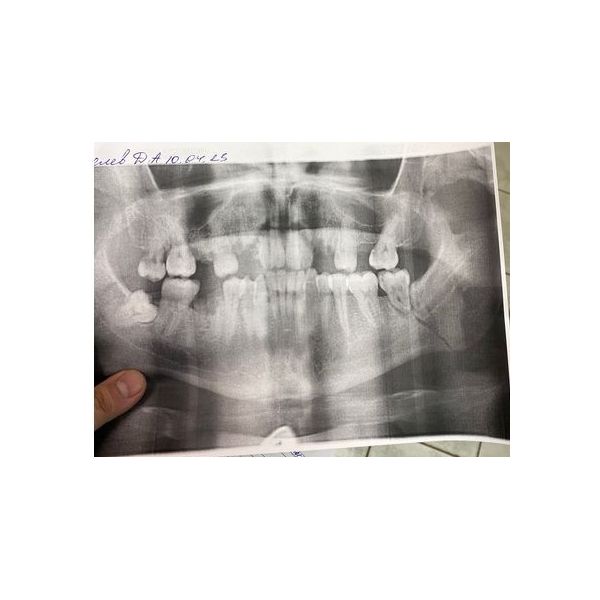

Ортопантомография (панорамный снимок) показал нарушение целостности кости в области зуба 3.7: он находился на линии перелома.

Травматический ангулярный перелом нижней челюсти слева со смещением.